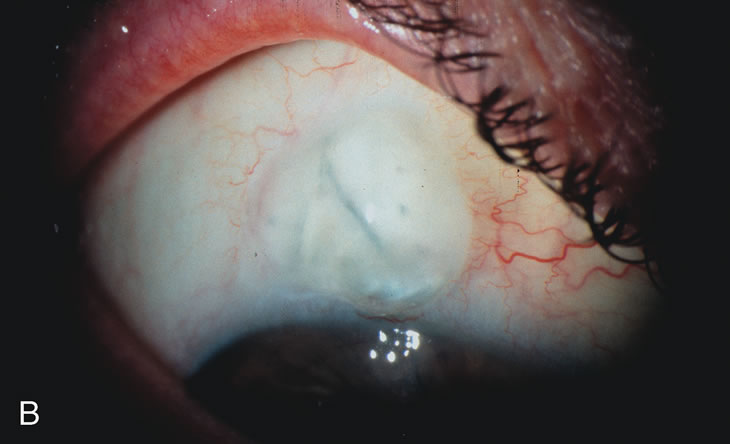

Fig. 3. Partial bleb failure following clear corneal phacoemulsification with foldable IOL. A. Preoperative bleb appearance prior to temporal lens extraction. Preoperative IOP was 12 mm Hg on no antiglaucoma medications. Time from 5-FU trabeculectomy surgery to lens extraction was one year. B. Bleb appearance 2 months after clear corneal cataract surgery with topical anesthesia. Following lens extraction, increased vascularity was noted along with decreased size of the filtering bleb. IOP increased to 20 mm Hg as early as 2 weeks after surgery, necessitating topical antiglaucoma therapy. C. High magnification view of bleb before lens extraction demonstrates diffuse pale bleb. D. High magnification view of bleb 2 months after surgery. There are vessels surrounding the nasal side of the bleb and the overall bleb size is smaller.

Cataract extraction by any technique performed in a patient with a pre-existing filter will have an effect on the previous filtering bleb.121–124 Bleb failure is more likely with ECCE compared with small-incision phacoemulsification.125 However, even patients undergoing topical anesthesia with clear corneal phacoemulsification and foldable IOL may experience bleb failure. One of three patients with a functioning filter and preoperative mean IOP of 12 mm Hg without antiglaucoma medications experiences bleb failure after lens extraction (Table 2). These patients require long-term drug therapy or bleb needling to control IOP. 126 Additional incisional glaucoma surgery may eventually be required in up to 10% of patients.127 Intraoperative iris manipulation may cause significant breakdown of the blood–aqueous barrier, resulting in inflammation that causes bleb failure. Even after uncomplicated clear corneal phacoemulsification, IOP may increase an average of 2 to 3 mm Hg due to bleb fibrosis.128 Approximately 20% of filtered patients require a long-term increase in glaucoma medications following uncomplicated clear corneal phacoemulsification with a foldable copolymer acrylic IOL129 (Fig. 3). In situations in which the bleb is not working at all, the eye will have a postoperative pressure spike that mimics that in the patient not having had a prior filtering procedure. In situations in which the bleb is marginal, the pressure spikes tend to be lower, and the final postoperative IOP tends to be around 50% higher than it was preoperatively. These patients require combined procedures in order to reestablish long-term filtration. In situations in which the bleb is very thin, polycystic, and associated with an IOP around 5 to 8 mm Hg on no antiglaucoma therapy; uncomplicated cataract extraction will have a minimal effect on the level of IOP. Patients with functioning glaucoma drainage implants usually have minimal long-term changes in IOP after uncomplicated cataract extraction.130